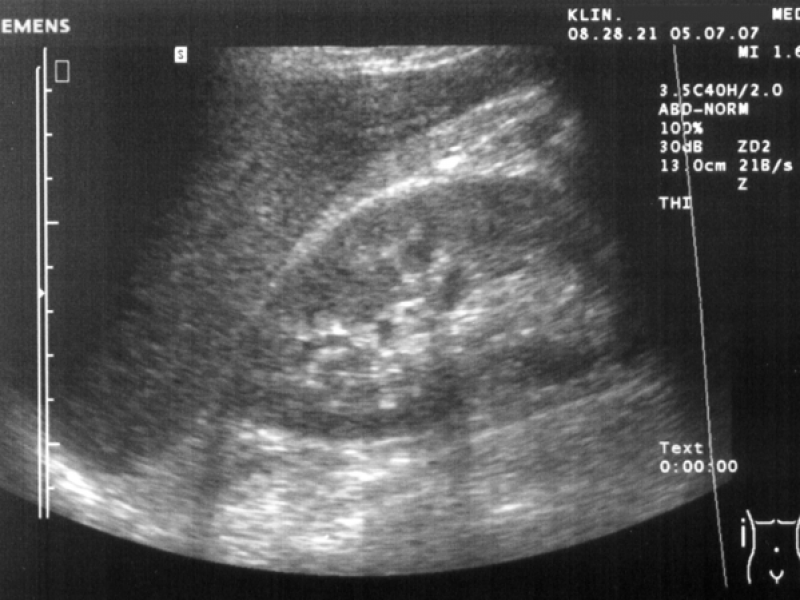

L’échographie abdominale est un examen médical qui utilise des ondes sonores à haute fréquence pour visualiser les organes et structures situés dans la cavité abdominale. Il permet aux professionnels de santé d’obtenir des images en temps réel d’organes à l’intérieur du corps.

Contrairement à d’autres méthodes d’imagerie, ce type d’échographie n’utilise pas de rayons X. L’objectif est d’identifier des anomalies qui pourraient expliquer des symptômes cliniques. L’échographie abdominale ne nécessite aucune incision et ne provoque aucune douleur.

L’échographie abdominale est un examen simple et rapide, réalisé dans des conditions normales. Le patient se trouve en position couchée sur le dos sur la table d’examen. Un gel conducteur est appliqué sur la peau de l’abdomen pour améliorer la transmission des ondes sonores. Le radiologue passe ensuite un transducteur à ultrasons sur la peau en le déplaçant avec soin. Cette sonde émet des ondes sonores qui rebondissent sur les structures internes et sont captées pour créer des images en temps réel sur un écran. Pendant l’examen, il peut être demandé au patient de retenir sa respiration ou de changer de position pour obtenir des vues claires. L’examen ne nécessite aucune préparation complexe, bien qu’un jeûne de quelques heures peut-être parfois demandé.